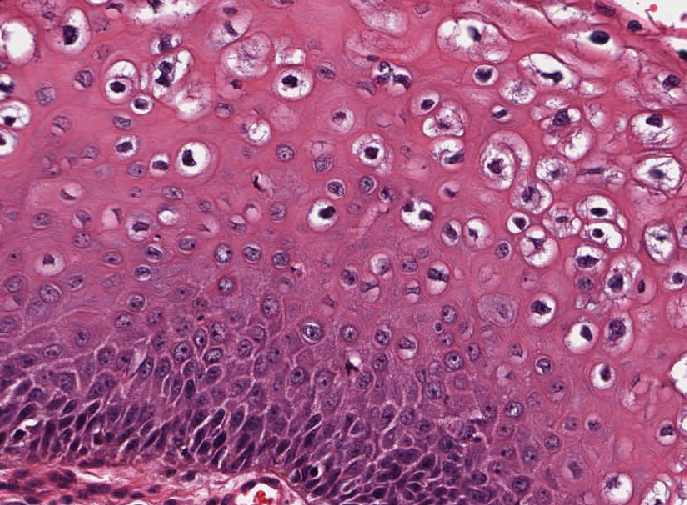

Microscopic (histologic) description

- Resembles condyloma acuminatum

- Diagnostic criteria

- Well formed papillae with a prominent central fibrovascular core

- Hyperkeratosis with parakeratosis and marked acanthosis

- Koilocytes on upper third of the squamous epithelium

- Chronic inflammatory infiltration

- Local extension and displacement of surrounding tissues but no evidence of dysplasia / invasion (WHO Classification of Tumours Editorial Board: Digestive System Tumours, 5th Edition, 2019)

- Low mitotic rate, usually confined to the basal layer with no abnormal mitoses (Histopathology 2017;70:938)

- About 30 - 35% may develop an invasive component; especially in high risk HPV positive cases (Virchows Arch 2020;476:543, Dis Colon Rectum 1989;32:481)

Microscopic (histologic) images

Lymphadenopathy seen in conjunction with a bulky anovaginal tumor characterized by parakeratosis, superficial koilocytosis, HPV ISH positivity and minimal squamous atypia as seen in this image is most likely due to